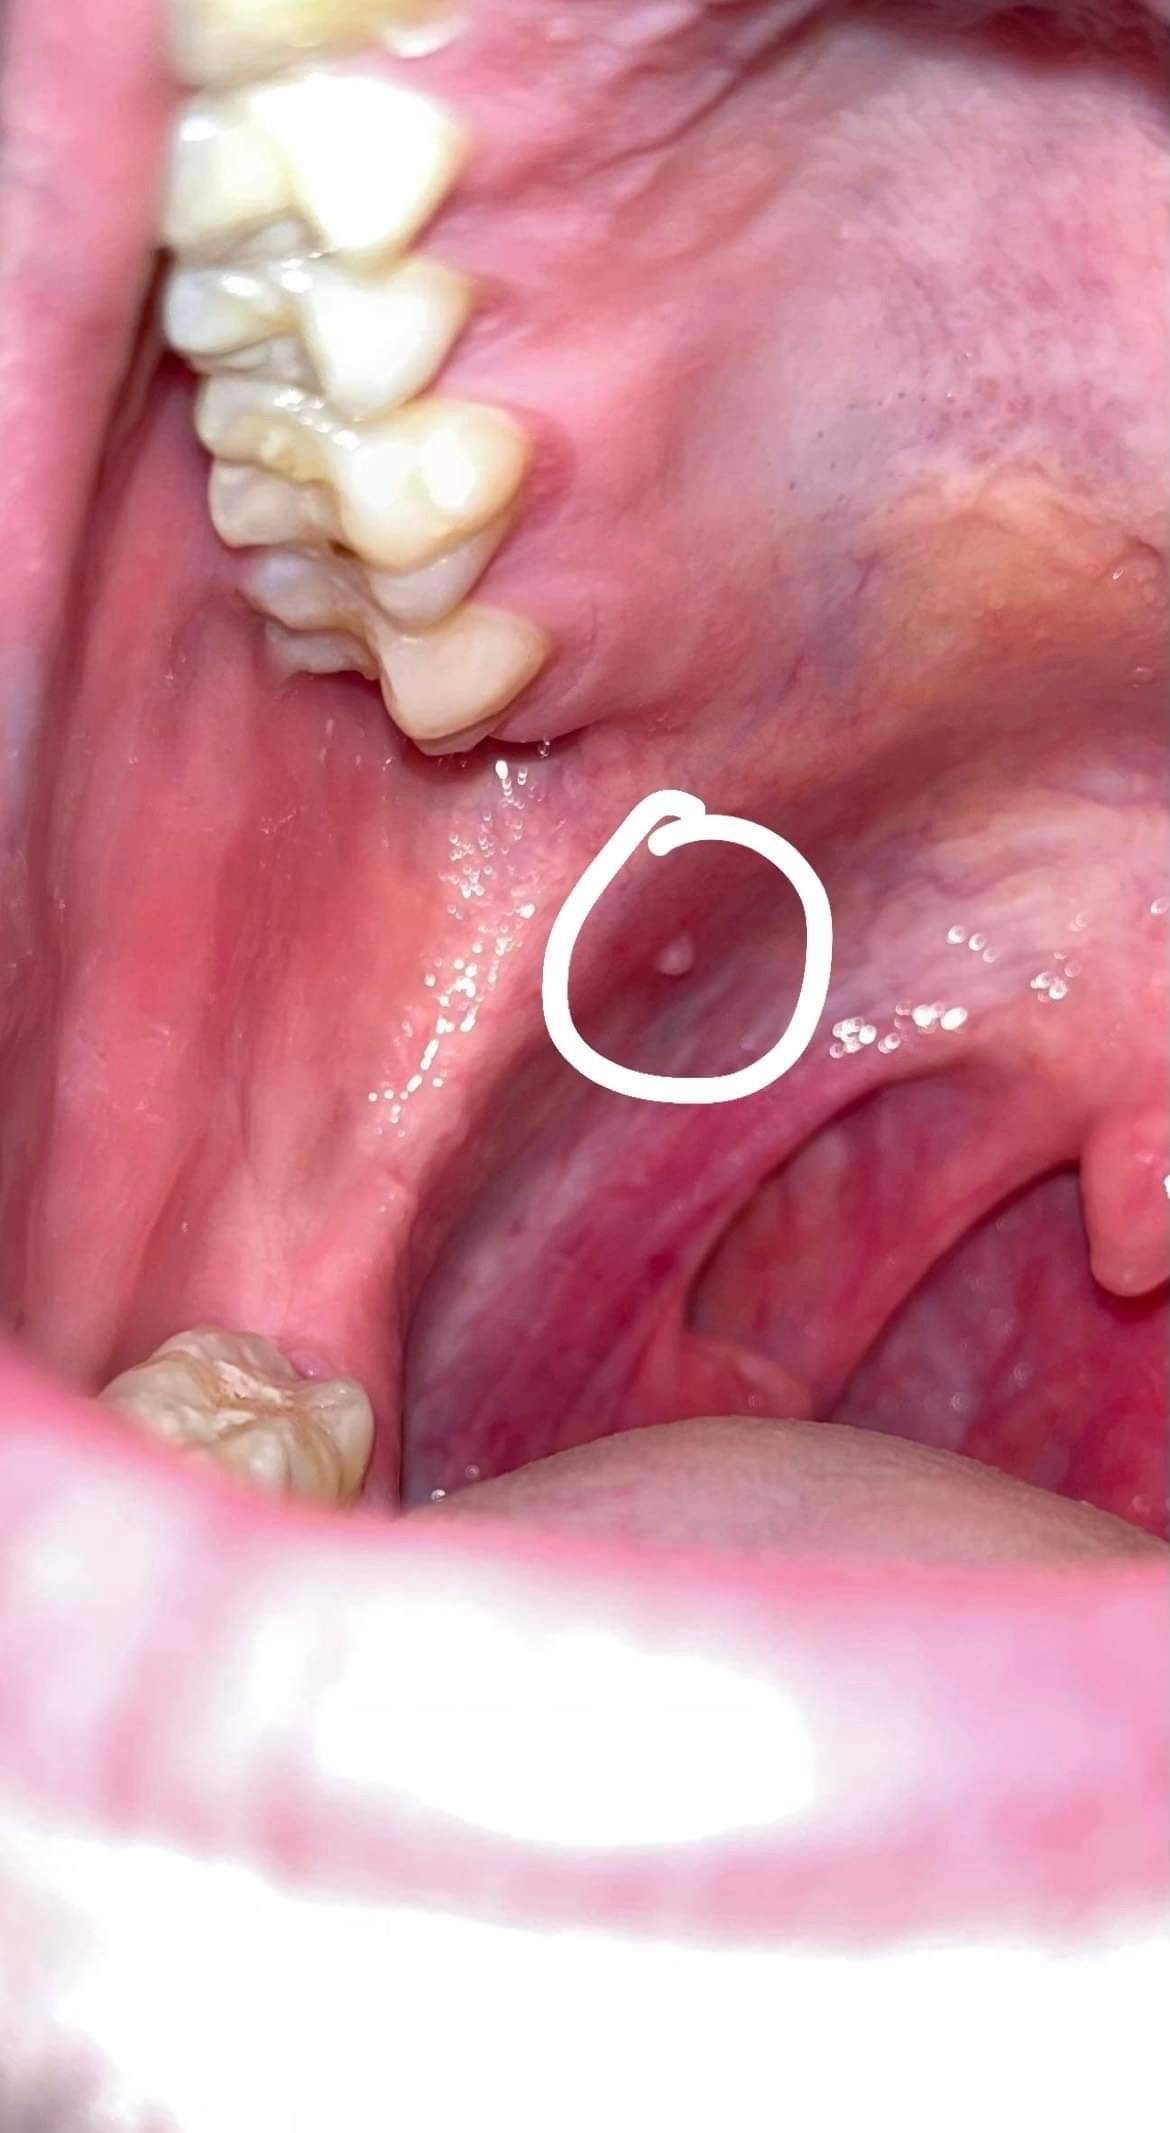

Salut, ce matin je me suis levé et en déjeunant j’ai eu une sensation désagréable à l’arrière droite du palais mou, je suis allé checker et j’ai vu cette petite boule

Je regarde souvent ma bouche donc je suis sûr qu’elle était pas là il y’a une semaine par exemple

Pour le contexte je sors de 2 jours de maladies (nausées, mal de ventre, courbatures) et sinon je prends un traitement désensibilisant contre les acariens qui se présente sous la forme d’antigènes tout les matins, mais ça ne m’a jamais fais ça…

Ah et je suis un peu stressé aussi